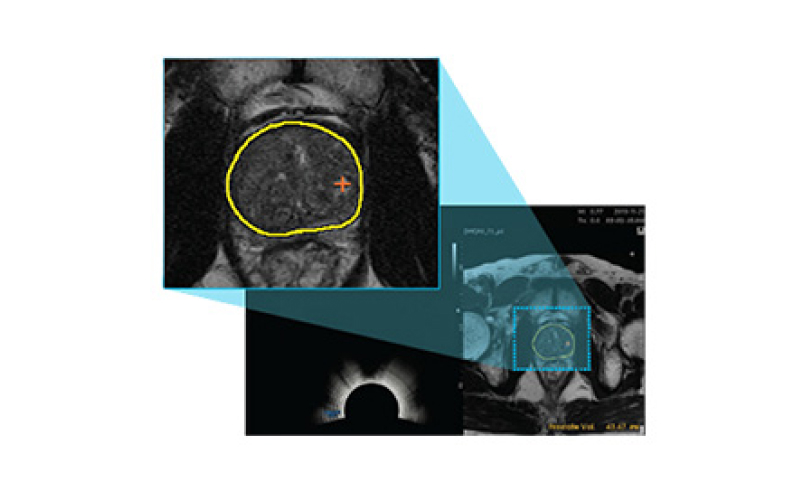

전립선을 자동으로 분석해 경계 분할

3D 영상

병변 정확 탐지

최첨단 AI와 3D 융합 영상으로 진단 정확도를 혁신적으로 높인 골드만만의 특별한 조직검사입니다.